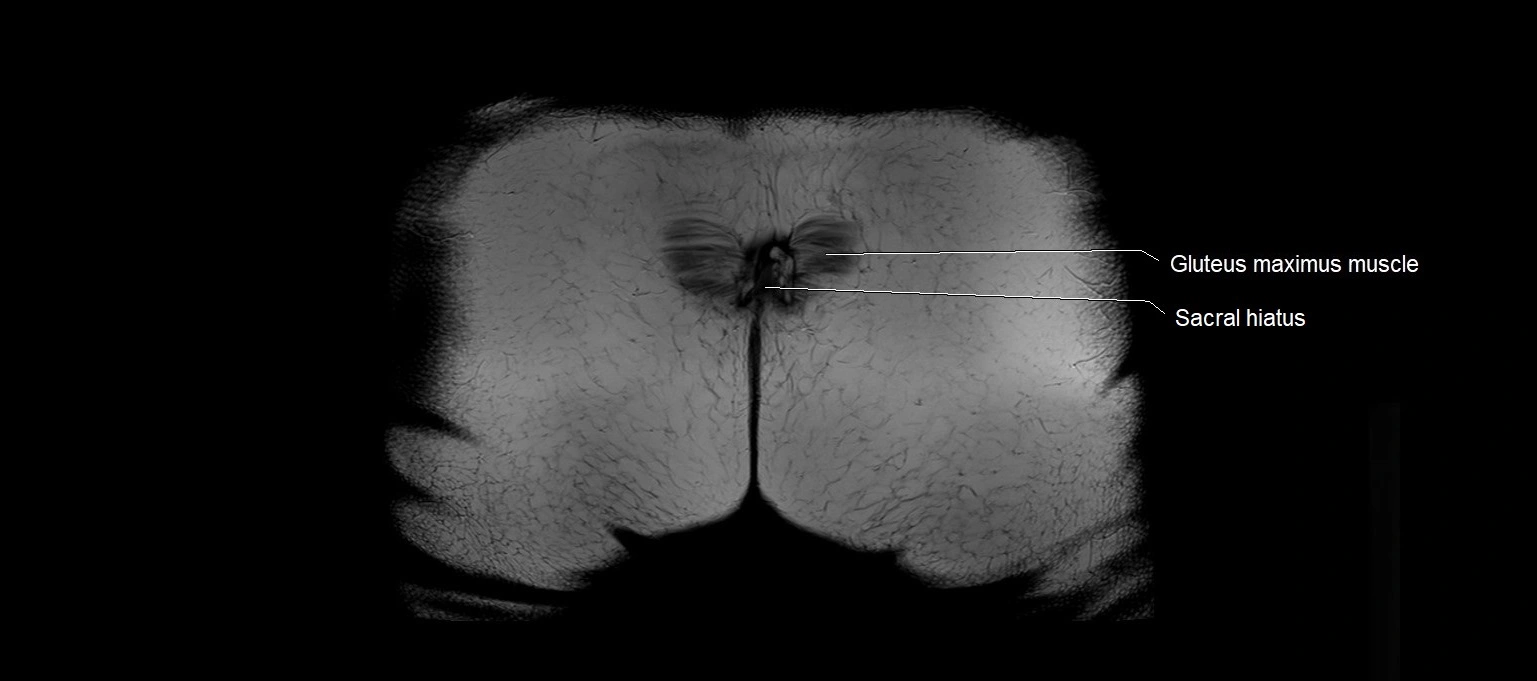

- Sacral hiatus